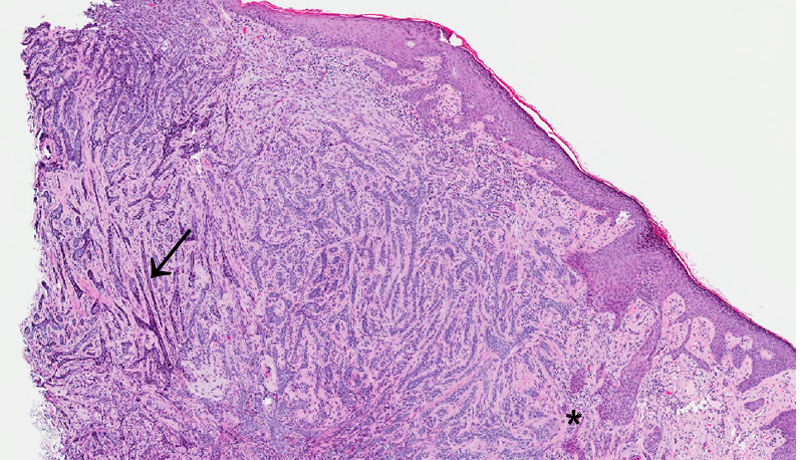

DISEASE: Basal cell carcinoma

PATHOGENESIS: Tumor cells originate from stratum basale or stratum germinativum of the epidermis.

HISTOLOGY FEATURES: Cords or Islands of basal cells with nuclear palisading of peripheral cell layer in the dermis. Retraction artifact may be seen as an empty space between the stroma and tumor island. Morpheaform (sclerosing type) shows islands and cords of flattened tumor cells in the dermis.